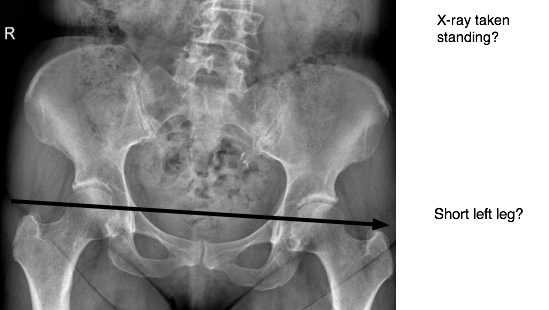

To get the hips level we first have to know how unlevel they are. Go to a chiropractor and get a set of standing x-rays. These are taken under the effects of gravity. Only chiropractors take standing x-rays. Chiropractors understand the relationship of structure vs. function.

Can you see how unblevel hips throws you out of balance?

The correction is easy. I take accurate measurements on how unlevel the hips are. I will need to put a heel insert inside the shoe to correct this. Sorry – not everybody is level. I even have to have a heel lift in my left shoe.